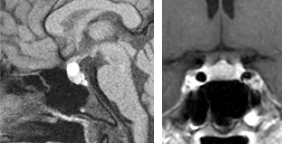

(外来で画像検査のみで経過観察している症例)

(嚢胞性病変;液体が主体の病変は視神経への圧迫が少ないため症状をきたすことはなく、経過観察で十分なことが多いです。このような病変は下垂体腺腫だけでなく、ラトケ嚢胞も鑑別診断となります。)